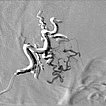

The microcatheter was advanced directly into the nidus. After visualization of the nidus, immediate direct venous outflow (DSA, venous phase) from the lesion via dilated veins. This confirms the diagnosis of an AVM.

DSA image depicting the arterial inflow, nidus with small arteriovenous fistulae, and venous outflow of the AVM before embolization. The complete angiomorphology of the AVM, at this point untreated, is easily visible.